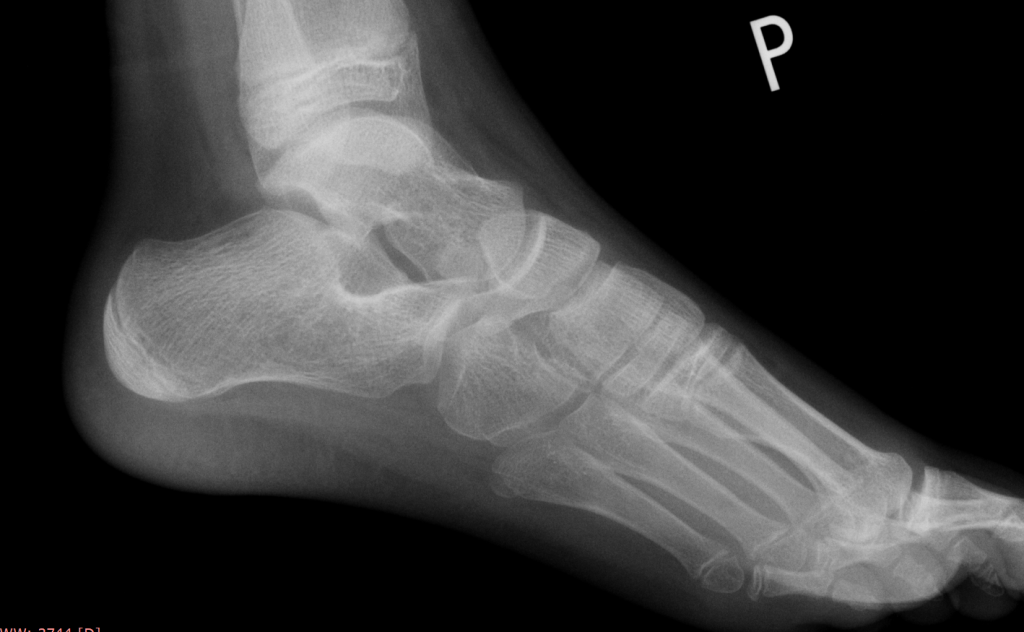

W Ultragen w Krakowie wykonano badanie USG stopy, które pozwoliło wykryć koalicję włóknistą z towarzyszącym pogrubieniem tkanek miękkich. USG jest szczególnie przydatne w:

• ocenie tkanek miękkich,

• wykrywaniu koalicji włóknistych i chrzęstnych,

• różnicowaniu przyczyn przewlekłego bólu stopy.

Uzupełniające badanie rezonansu magnetycznego (MR) wykazało:

Połączenie USG i MR pozwala na pełną ocenę anatomiczną i funkcjonalną stopy, co ma kluczowe znaczenie dla dalszego leczenia.